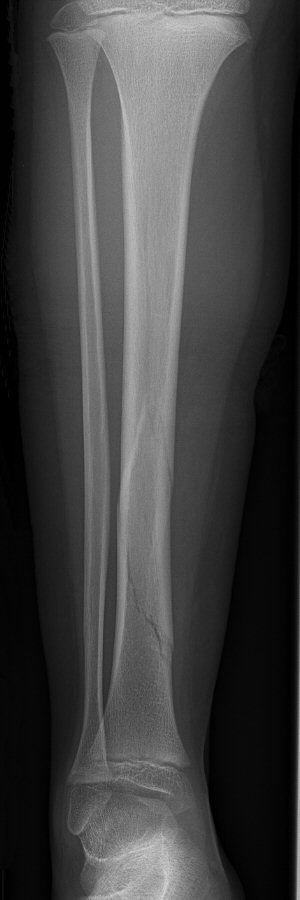

Tibiafraktur hos 7-åring, behandlades med gipsstövel